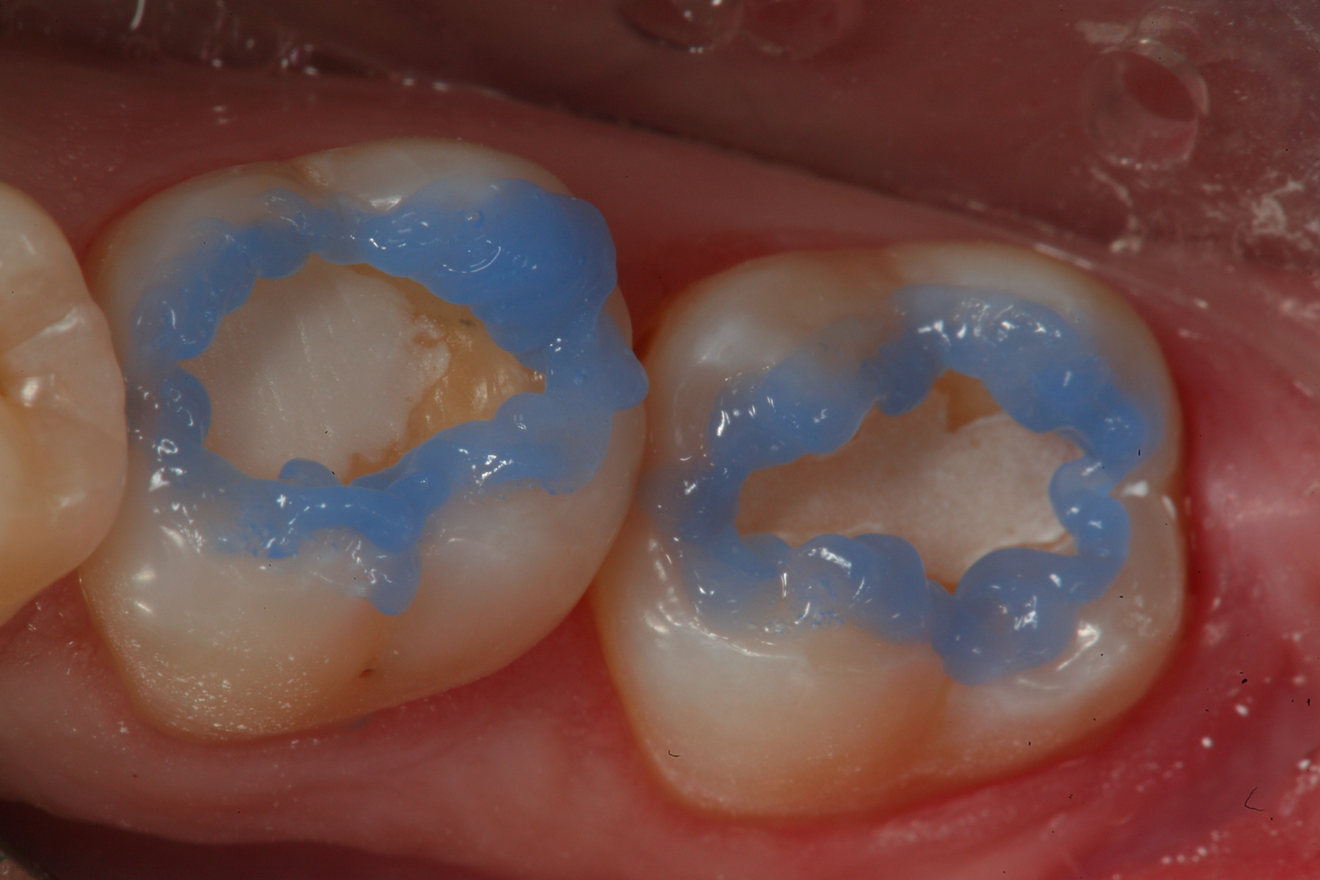

Fig 11. After removal of the existing restorations and associated recurrent decay, both cavities are very deep and there is a pinpoint pulpal exposure on tooth No. 19.

Figure 11